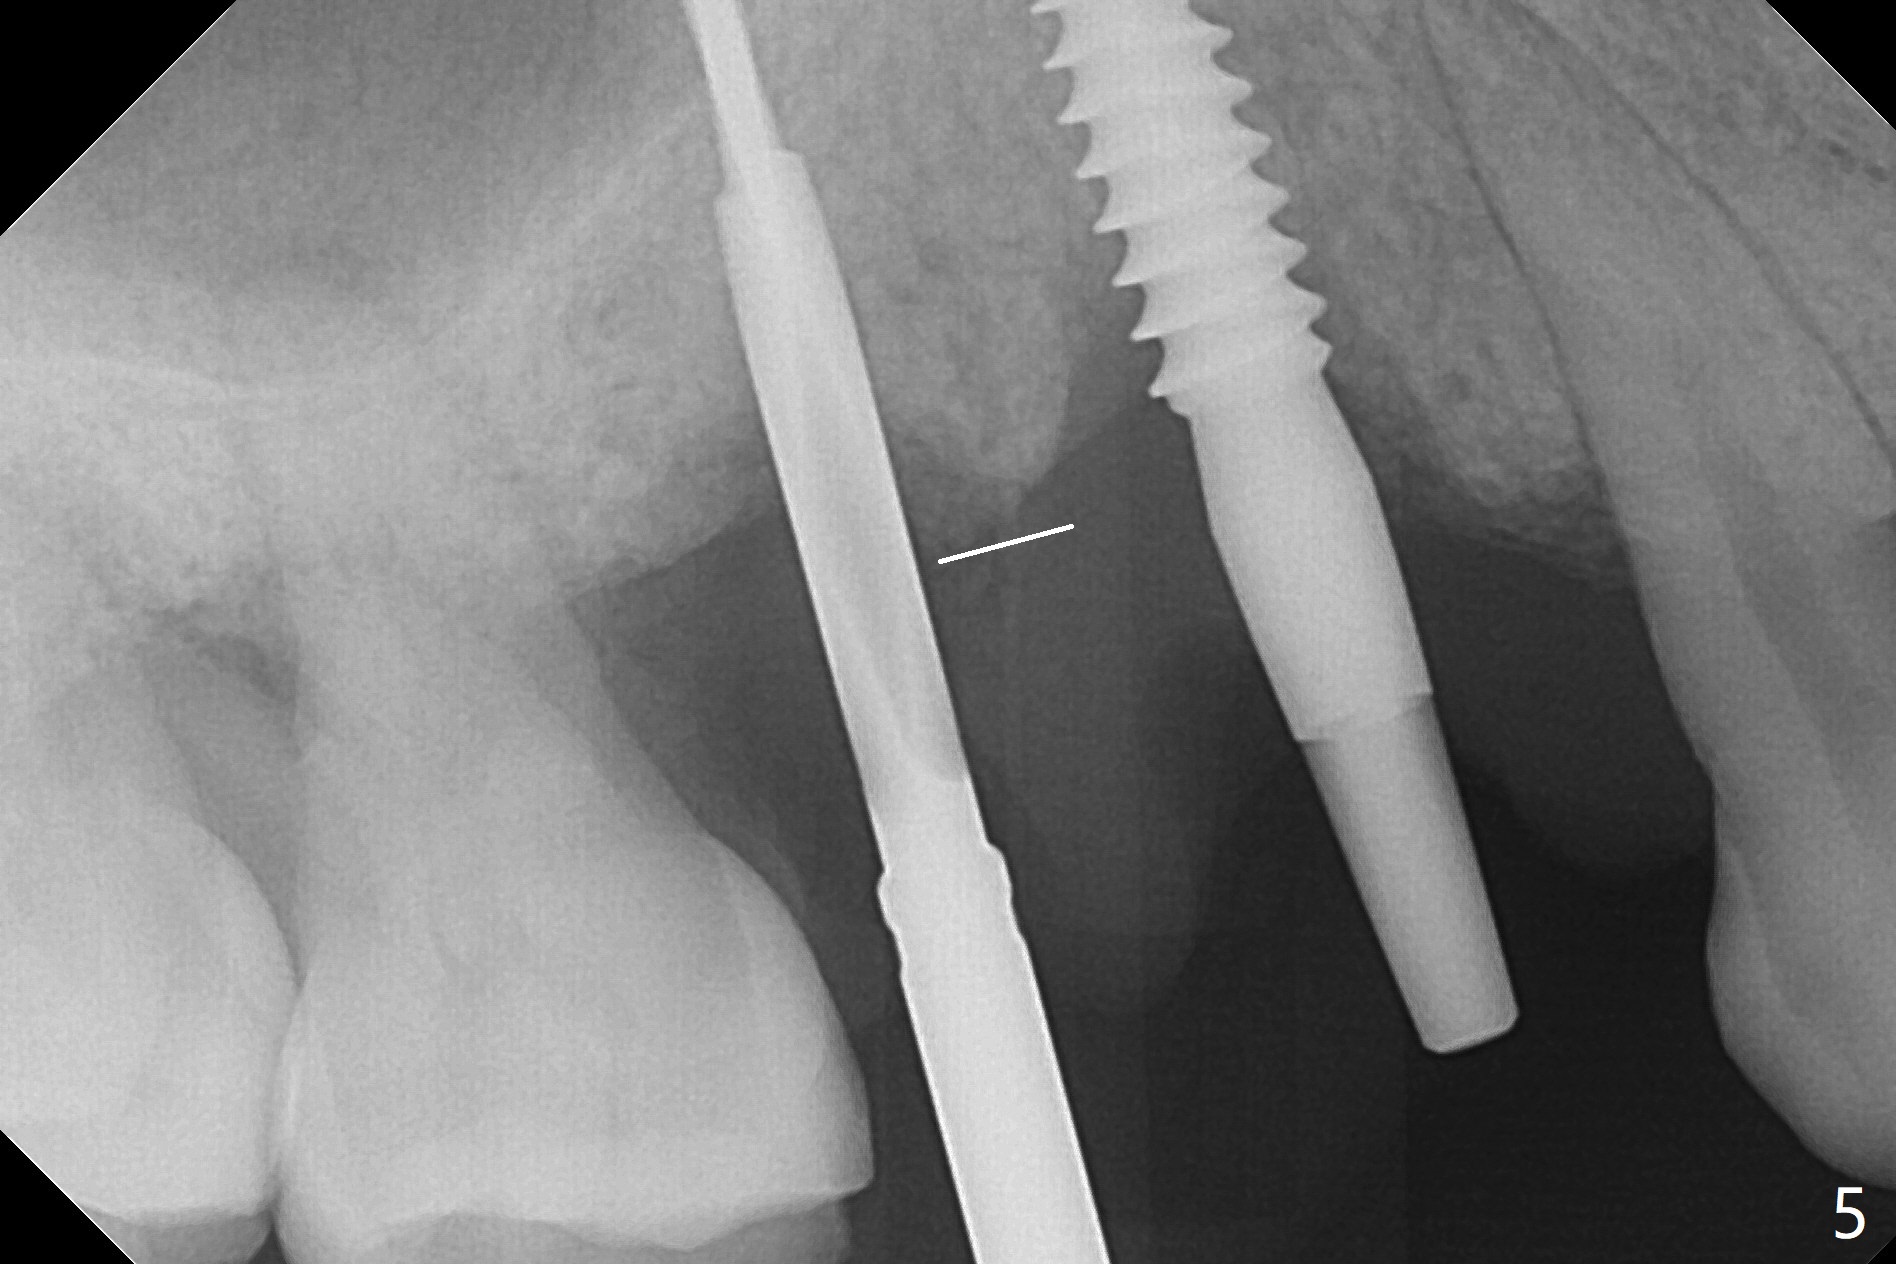

术前CT显示右上4牙槽骨比5窄(图一,二),3.5毫米植体比较合适,况且牙龈厚,基台长的一段式植体显得得当。为了取得最好的植体方位,4先拔除(图三),种植(图四),调整后者深度后,拔除5(术前征求病人同意),开始钻洞(图五),完成种植(图六)。粘性骨粉不仅放置于植体周围,而且6牙根近中(图七),4/5牙槽嵴和龈乳头(P)之间,减少术后龈乳头萎缩(图八:*)。制作两个分开临时牙冠,有利于维持龈乳头。对于病人来说,临时牙冠帮助咀嚼,而对侧拔牙创无法吃饭。术后3个月两个分开临时牙冠(其中一个龈方移位(图九:箭头)保持龈乳头(*)和牙龈外形(图十:*)。临时牙冠取出后,调整基台高度,少量钛屑(不妨大局)附着在健康的牙龈沟(图十一),再次显示两个基台之间龈乳头(图十二:*),衬里,修整的临时牙冠又插回牙龈沟(图十三:箭头),继续维持软组织形态,准备一个月后,调整基台边缘(图十二:箭头),取模。术后五个月大部分骨粉依然保留在植体和邻牙周围,龈乳头退缩不多(图十四: P)。三个月后(术后六个月)钛削无影无踪(图十五,与图十一对比))。永久性牙冠周围空间慢慢会消失(图十六,使用临时性胶水)。